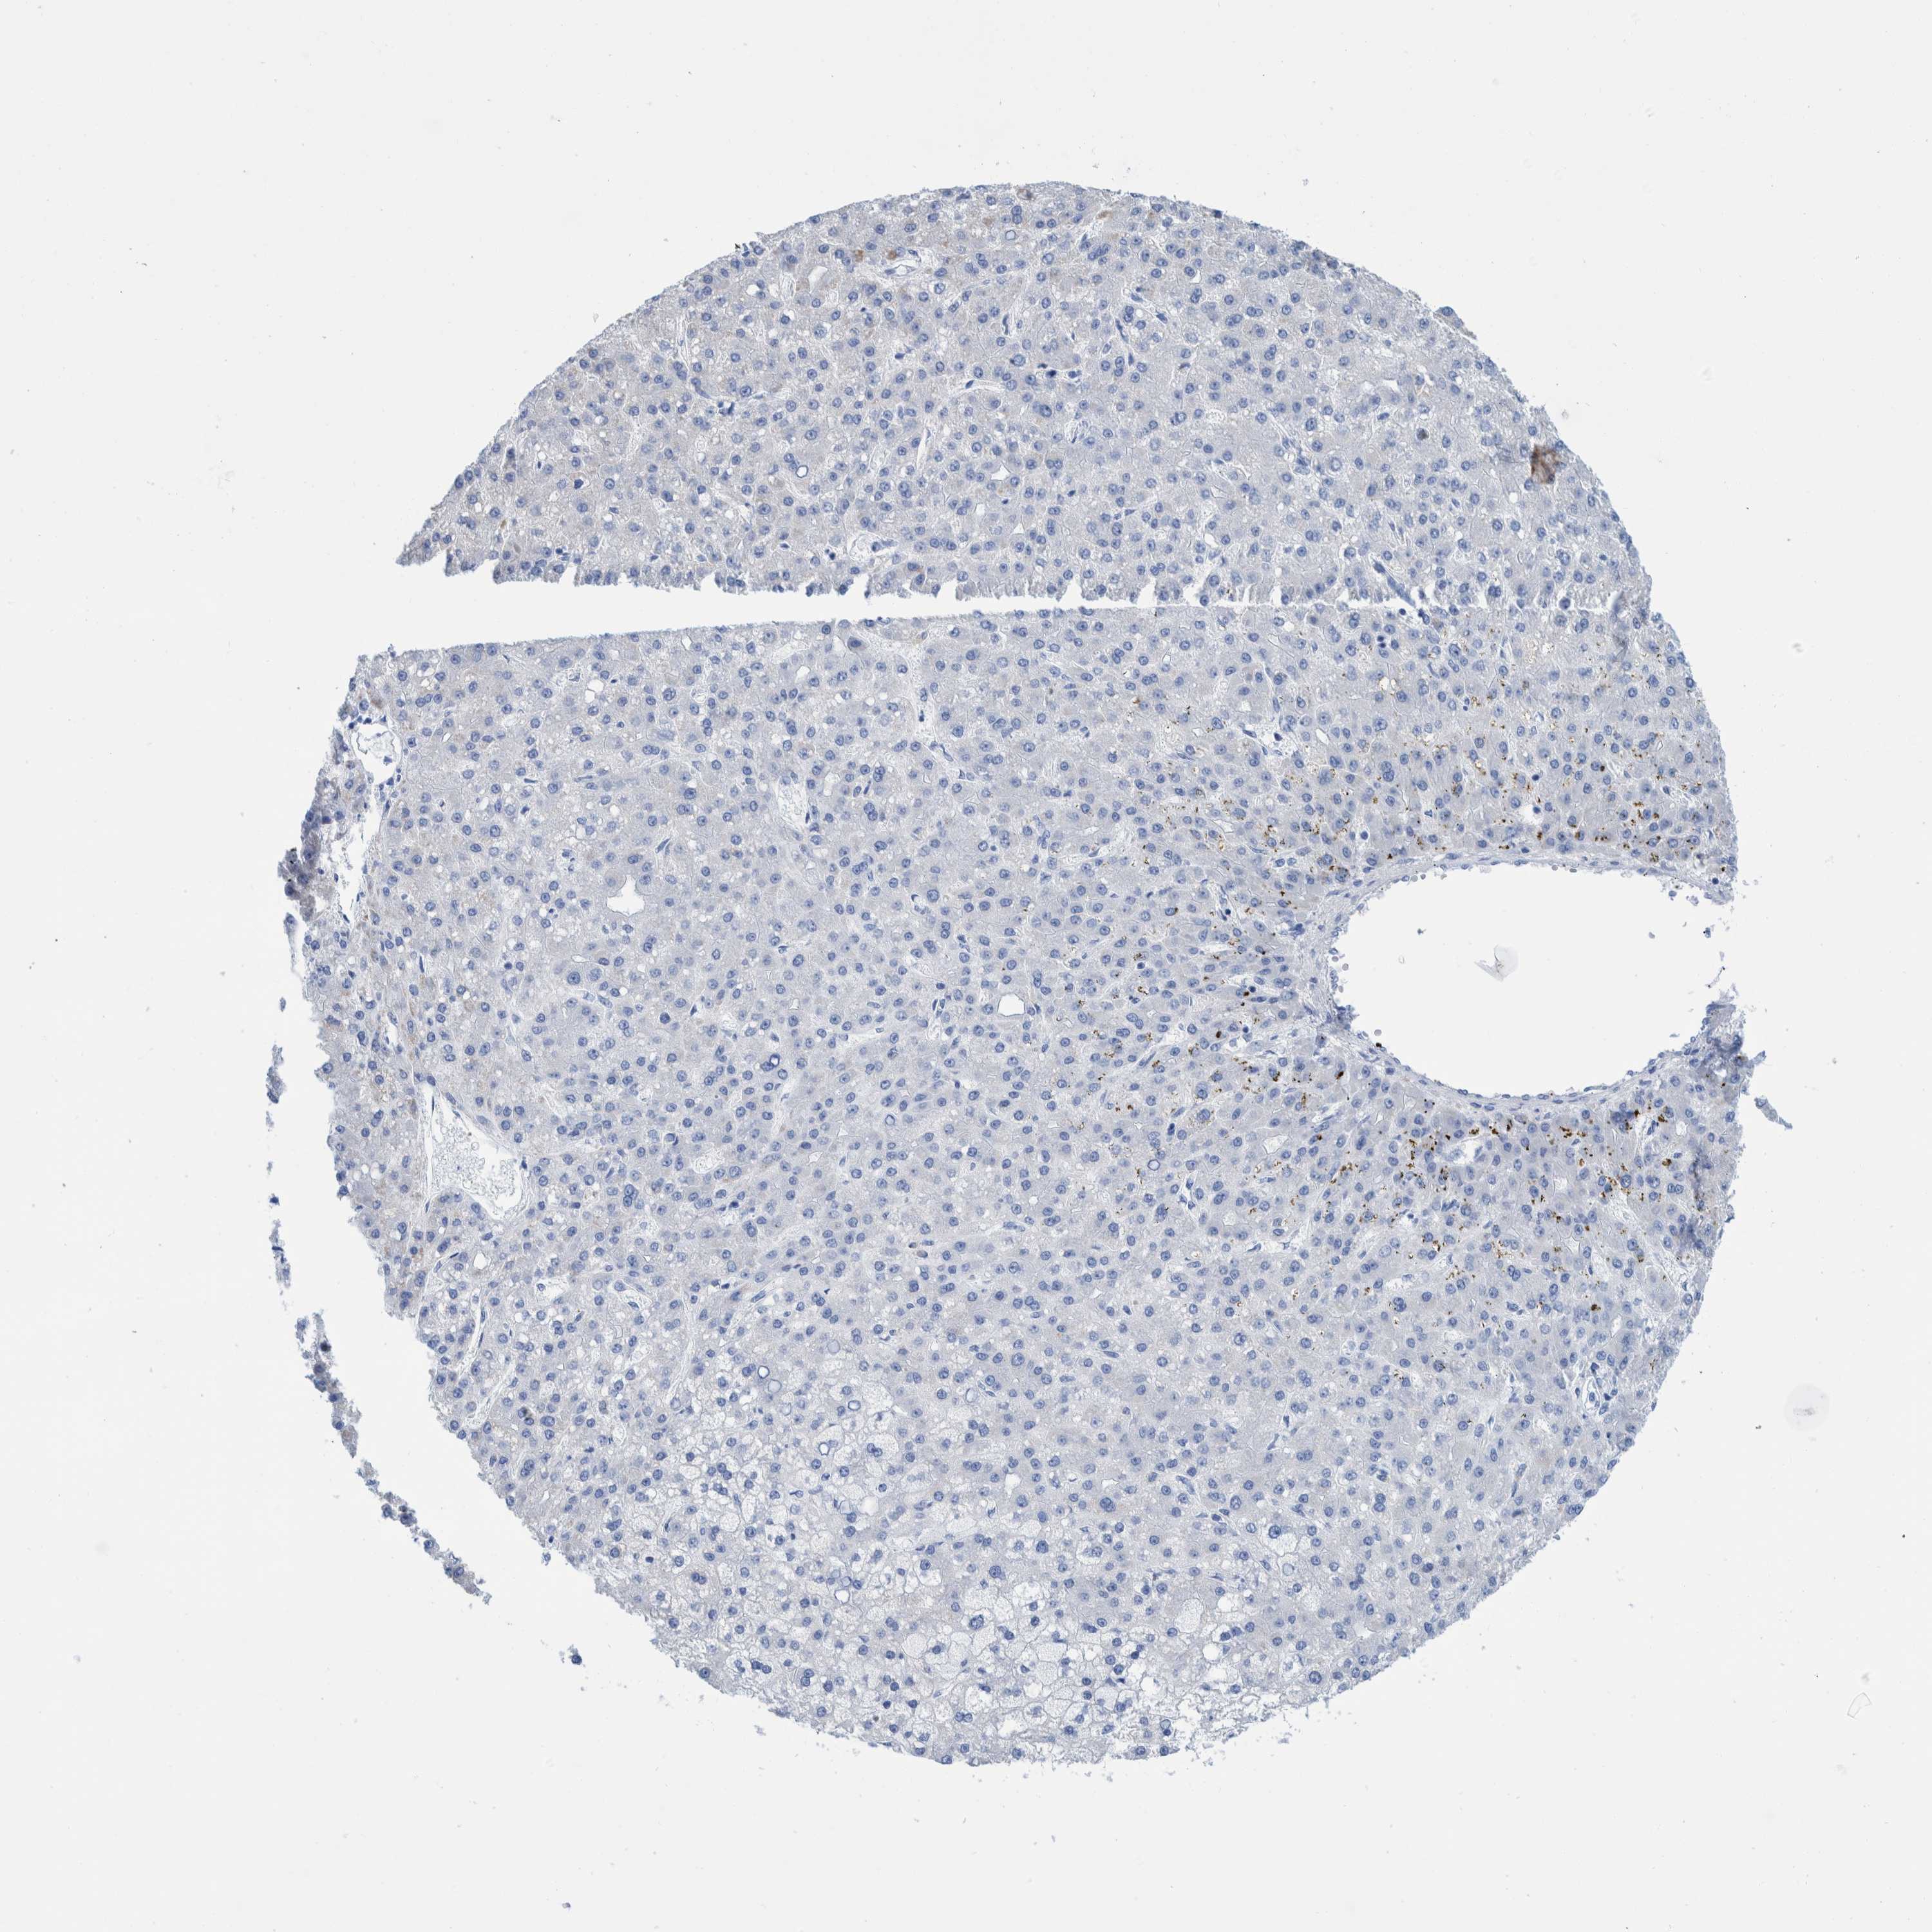

LIVER CANCER - Protein expressioni

A mouse-over function shows sample information and annotation data. Click on an image to view it in a full screen mode. Samples can be filtered based on level of antibody staining by selecting one or several of the following categories: high, medium, low and not detected. The assay and annotation is described here.

Note that samples used for immunohistochemistry by the Human Protein Atlas do not correspond to samples in the TCGA dataset.

Antibody HPA000452

Antibody HPA023040

Antibody CAB000134

Staining

High

Medium

Low

Not detected

Intensity

Strong

Moderate

Weak

Negative

Quantity

>75%

75%-25%

<25%

None

Location

Nuclear

Cytoplasmic/membranous

Cytoplasmic/membranous,nuclear

Carcinoma, Hepatocellular, NOS

Cholangiocarcinoma